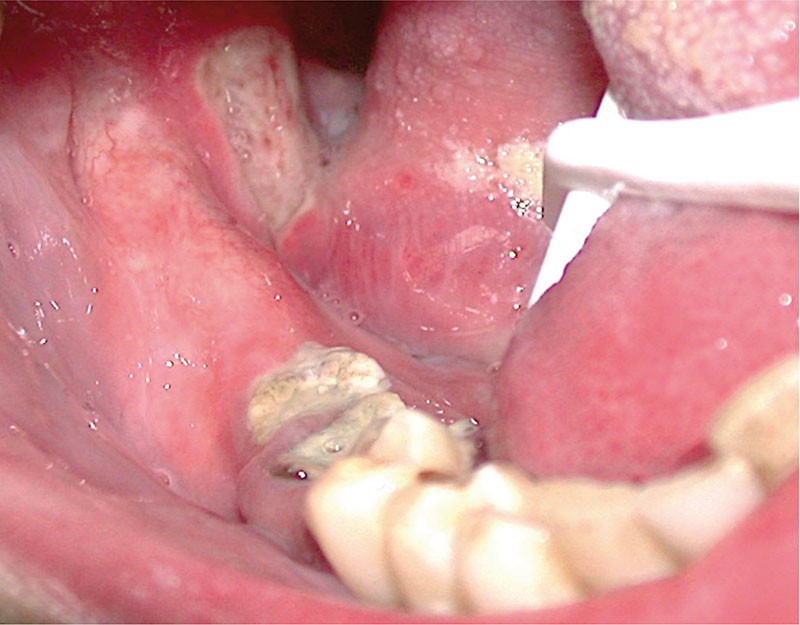

Les aphtes bucco-pharyngés sont des ulcérations spécifiques siégeant le plus souvent sur la muqueuse non kératinisée. On distingue les aphtes miliaires, géants et vulgaires. Les aphtes doivent être différenciés des ulcérations aphtoïdes qui sont secondaires à une cause générale le plus souvent. Les aphtes et les lésions aphtoïdes récidivantes doivent faire rechercher une cause générale et une maladie de Behcet. Le traitement des aphtes repose en première intention sur la corticothérapie locale et la prévention des récurrences sur un traitement par colchicine au long cours.

Les aphtes sont des ulcérations muqueuses spécifiques douloureuses, sporadiques ou récurrentes dont le traitement est le plus souvent simple et efficace.

DÉFINITION

Les aphtes sont des ulcérations de la muqueuse buccale spécifiques, secondaires à une vasculite leucocytoclasique. Les aphtes buccaux sont sporadiques ou récurrents dans l’Aphtose Bucco-Pharingée Récidivante (ABPR). La forme clinique la plus sévère de l’ABPR est la grande aphtose de Touraine plus connue sous le nom de maladie de Behcet.